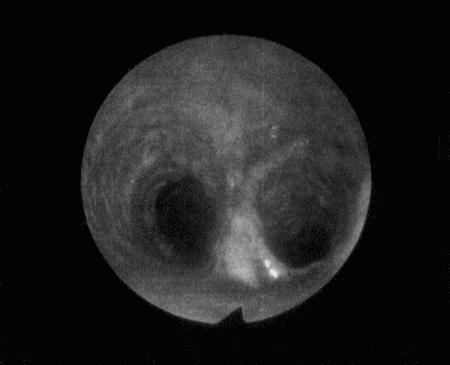

Вагинальная эндоскопия

Прекращение секреции эстрадиола фолликулами и переход их к секреции прогестерона приводят к снижению как отечности, так и васкуляризации слизистых оболочек, что сопровождается выраженным изменением характера вагинальных выделений, выявляемым с помощью вагинальной эндоскопии. На стадии проэструса слизистая оболочка становится более выпуклой и отечной, затем наблюдается ее уменьшение; по мере приближения овуляторного пика слизистая сжимается и бледнеет, в некоторых случаях становясь практически белой (фиг. 1.1). Перечисленные изменения свидетельствуют о приближении стадии, характеризующейся постепенным повышением концентрации прогестерона перед овуляцией и последующим наступлением фертильного периода. Эти изменения легко узнать, имея даже небольшую практику (фиг. 1.3), кроме того, они настолько воспроизводимы, что по набору признаков их можно оценивать полуколичественно. Вагинальная эндоскопия весьма полезна в определении оптимальных сроков вязки. По окончании фертильного периода, т. е. в начале метэструса — слизистая оболочка влагалища бледнеет и истончается, складки становятся закругленными — и что, вероятно, является наиболее характерным признаком, — слизистая в переднем отделе влагалища выглядит раздраженной и при прикосновении быстро сжимается, образуя розетку.

Фиг. 1.3.

Эндоскопическое исследование слизистой влагалища. Динамика изменений на протяжении цикла: (а) проэтрус — розовая окраска и отечность; (b) начало эструса — слизистая бледнеет, отек начинает уменьшаться (обычно перед пиком ЛГ); (c) середина эструса — слизистая бледная, уменьшение отека (сморщивание) явно выражено, что соответствует середине фертильного периода; (d) начало метэструса — видны закругленные складки, при прикосновении слизистая смыкается, образуя розетку (е) (см. Приложение)